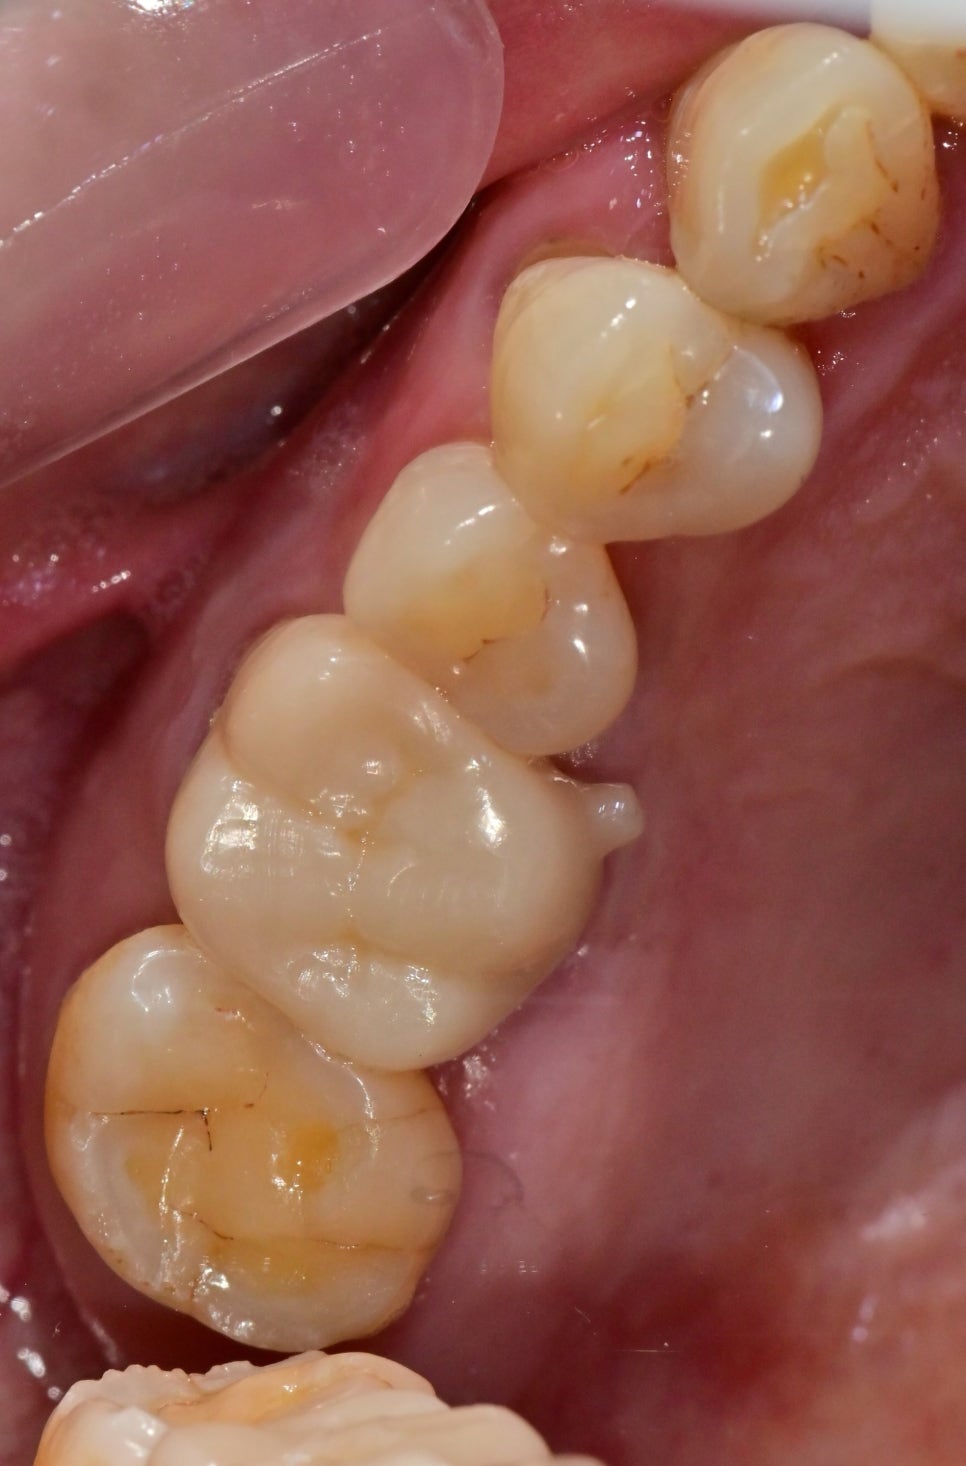

처음 환자분을 검진하기 전 사진을 봤을 때

왼쪽 치아가 다수 상실된 상태에서 우측으로 주로 씹다 보니 가장 일을 많이 하는 치아인

첫 번째 큰 어금니가 망가진 것이 보였습니다.

구내 사진을 찍고 검진을 했을 때 이 치아는 예후가 좋지 않다고 설명을 드렸습니다.

임시로 사용했을 때의 사진입니다.

다행히 여러 번의 신경관 소독을 통해 입천장 쪽의 고름 주머니는 사라지고, 통증도 줄어들으셨지만